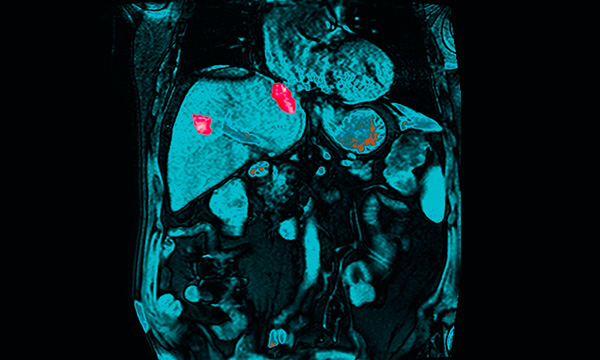

This is a summary of the peer-reviewed article: Abdominal X-rays in children: indications, proced